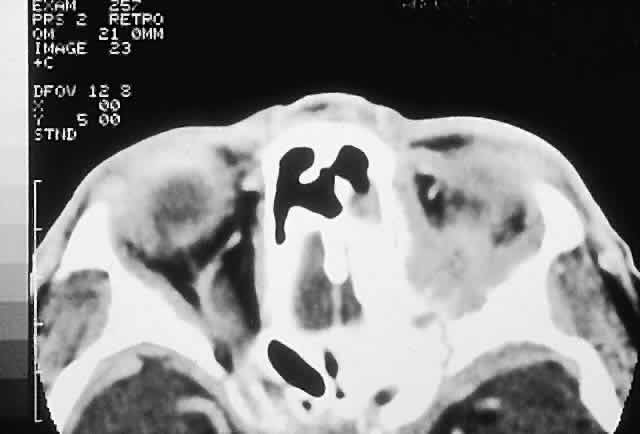

IMAGING. A mixed lytic and sclerotic mass with indistinct margins is the usual CT appearance (Fig. 9). Soft tissue infiltration of the orbit may also be evident, and the mass may contain foci of mineralization, producing fluffy densities. MRI can be of value in delineating the extent of any soft tissue component.12,116,117

Fig. 9. A painful right inferior orbital mass effect developed over several weeks in this 19-year-old man with a history of bilateral retinoblastoma treated with radiation therapy and chemotherapy. A and B. CT showed an irregular, largely sclerotic mass involving the orbital floor. He was treated with an en bloc orbitectomy and chemotherapy but died 4 years later from acute myeloid leukemia. C. Histology revealed a sarcomatous stroma with osteoid production forming lacelike patterns (hematoxylin-eosin, × 20). D. A high-power view of the sarcoma adjacent to extraocular muscle indicates that the anaplastic cells appear less atypical with incorporation into the osteoid, the so-called normalization of malignant osteoid (hematoxylin-eosin, × 50).